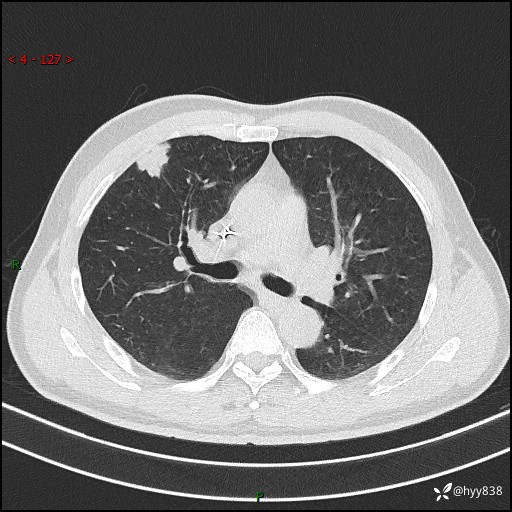

现病史:者10余天前因胸闷就诊于我院心血管内科,行胸部CT提示右肺上叶结节(24mm×16mm),考虑肿瘤性病变可能。无畏寒、发热、盗汗,无咳嗽咳痰,无咯血,无胸痛,无呼吸困难等不适,未予特殊处理。今为求进一步诊治,前来我院就诊,门诊以“肺结节待查”收住入院。 患者自起病来精神、食欲、睡眠尚可,体力下降,体重无明显变化。

胸部CT平扫+增强